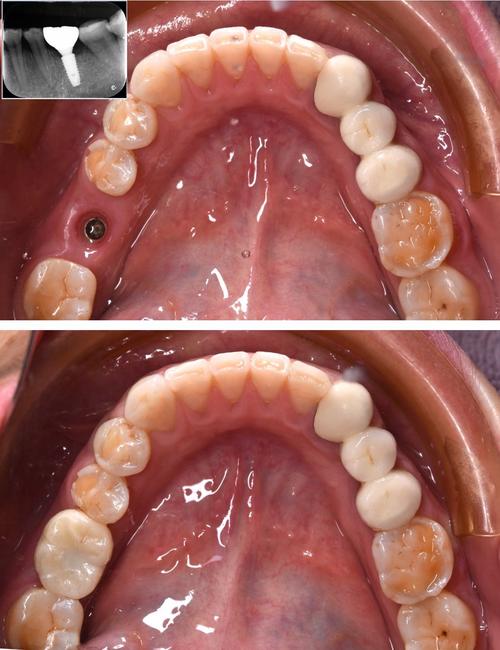

- 术后维护:术后1周、1个月、3个月复查,观察骨结合情况,3-6个月后待种植体与骨组织融合,更换永久牙冠(如全瓷冠)。